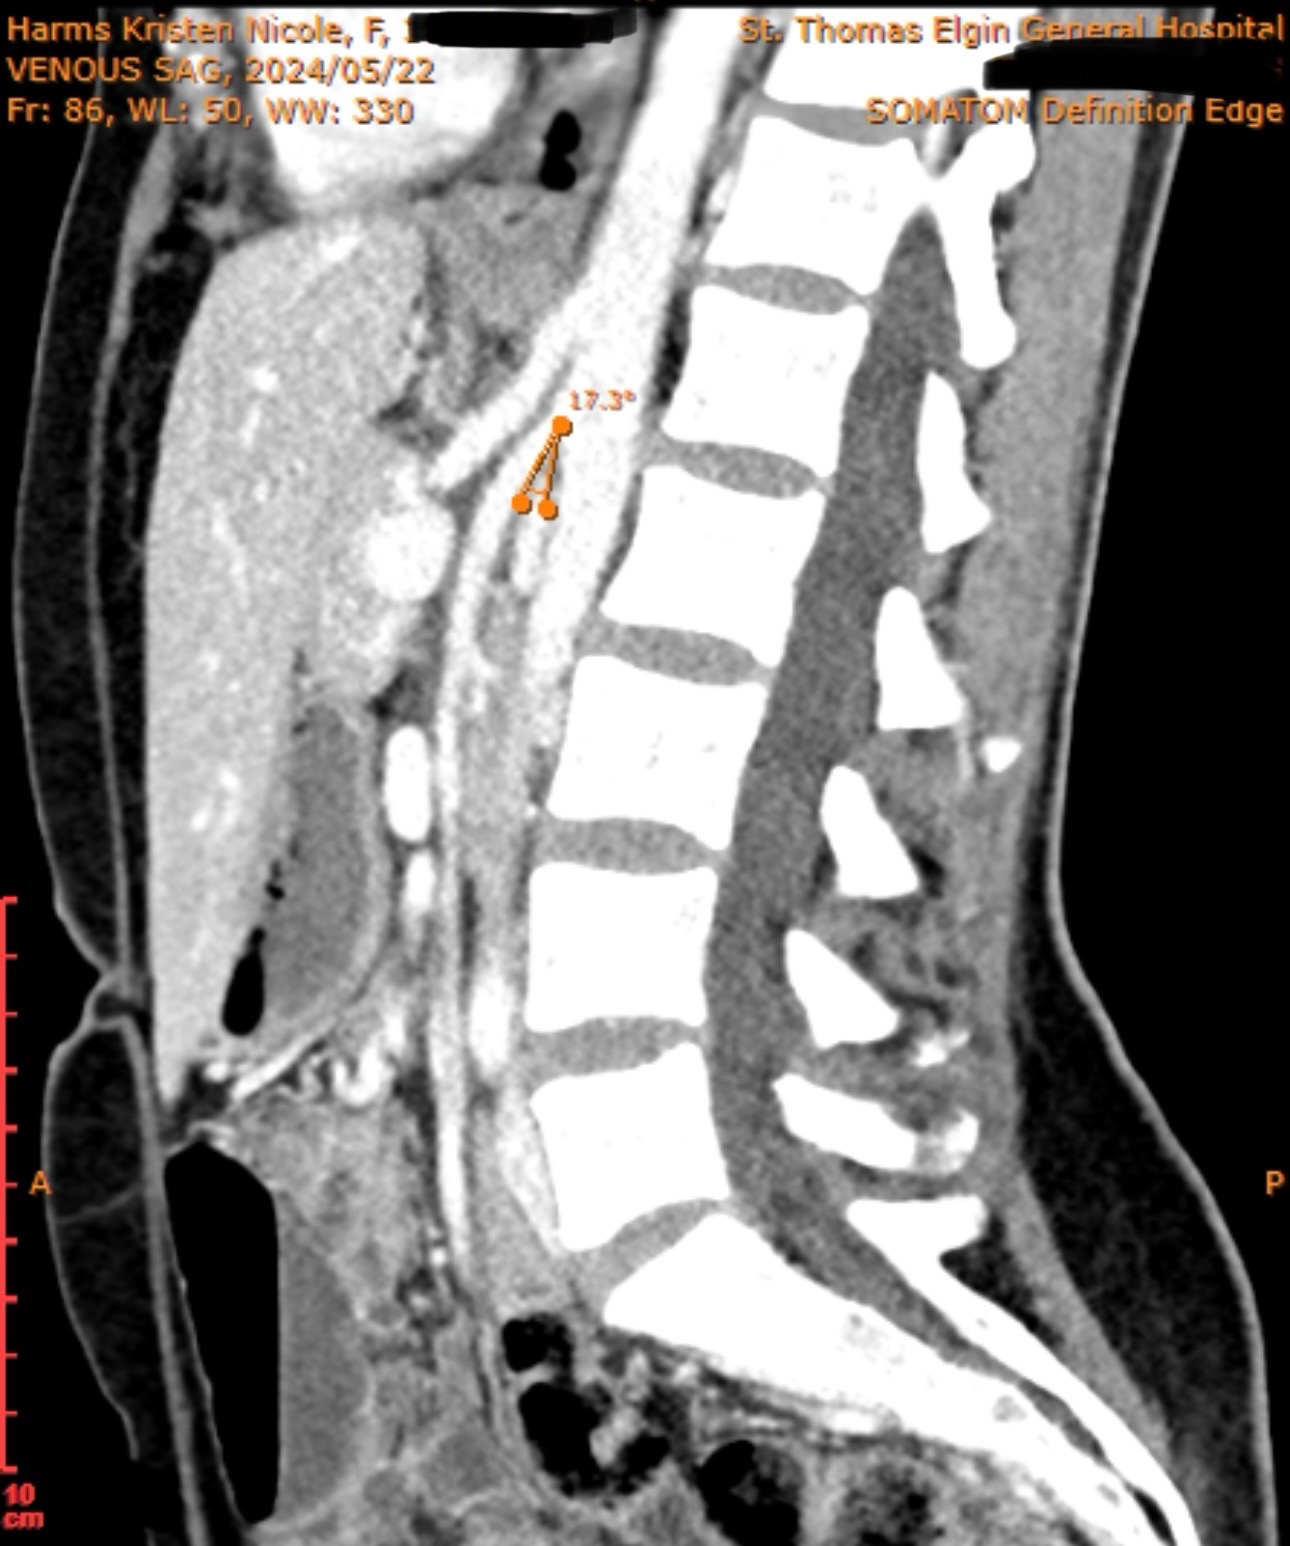

I was recently diagnosed with several rare vascular compression syndromes after years of misdiagnosis’s and progressing symptoms, including Superior Mesenteric Artery Syndrome (SMAS), May-Thurner Syndrome, and Nutcracker Syndrome. These conditions severely restrict blood flow to my digestive organs and block part of my duodenum, causing constant pain, extreme weight loss, and severe malnutrition. Despite trying every medical option available in Canada, I’ve been unable to access the life-saving surgery I need in a reasonable timeframe. Currently in Canada, there is only one surgical option that does not fix the compression and has an 80% failure rate. My doctor has been unable to find a surgeon even willing to treat SMAS as all claim it is too difficult to deal with and it is an extremely rare disorder. I have went from 161lbs, down to 100lbs, with severe gastro symptoms daily and constant pain, nausea and vomiting. I receive infusions for my iron, frequent b12 injections and high doses of vitamin d to try and keep my levels up as my malabsorption is so severe causing anemia. The SMAS causes food and acid to backup into my stomach, which has caused bad, long term gastritis. My body has been in ketosis long term as I am starving despite still maintaining adequate calories, I have muscle wasting, and severe fatigue along with many secondary complications from the SMAS. This has completely taken away my quality of life, and I am now suffering without any help in Canada for this condition.

SMAS can be fatal when left untreated. After extensive research and consultation, I have made plans to be treated by Dr. Alvear in the Philippines, who specializes in treating Superior Mesenteric Artery Syndrome. The surgery and recovery plan he offers provide the best chance for me to regain my health, nutrition, and quality of life. The procedure I am having done is known as the Alvear procedure. Unlike older surgeries that create a bypass and often fail long term, this procedure fixes the root cause by repositioning and freeing the duodenum (the first part of the small intestine) from the artery compression. The intestine is then moved to a healthier position on the right side of the abdomen to prevent future twisting or obstruction. The result is a restored normal digestive pathway, allowing patients to absorb nutrients and eat again without pain or fear.